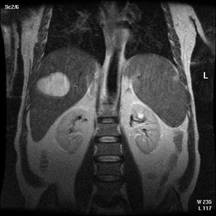

Īn stare de repaus protonii de H din corpul omenesc sunt orientati anarhic. Daca īi supunem unui cāmp magnetic static intens care actioneaza din afara corpului la o temperatura joasa, ei se aliniaza cu axul lor paralel sau antiparalel cu directia cāmpului magnetic. Sub actiunea unui alt cāmp exterior protonii īsi pierd orientarea si alinierea revenind la pozitia lor initiala de echilibru, trec printr-o faza de tangaj care consta īntr-o miscare de rotatie analoga miscarii unui titirez īn timpul careia emit un semnal de rezonanta receptionat de bobinele detectoare. Amplitudinea semnalului receptionat este proportionala cu numarul de nuclei din proba. Protonii de H care se vad mai bine sunt cei legati de apa si grasimi. Aceste doua medii dense īn protoni apar albe, osul (15 % apa) apare negru ca si plamānul. Fluidele īn miscare avānd protonii īn miscare au semnale foarte slabe.(jos-imagini rezonanta magnetica-abdomen, respectiv coloana cervicala)